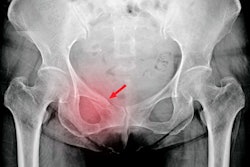

DEXA is used widely to measure bone mineral density in osteoporosis screening, but it has also proven effective in research for assessing whole-body and regional adiposity with reasonably high accuracy. Few studies, especially any in a large cohort of postmenopausal women, have compared the predictive accuracy of the measures, the authors wrote.

In this study, a team from nine U.S. centers investigated whether DEXA estimates of adiposity, specifically percentages of total-body and trunk fat (%TrF), in older women could improve risk prediction for cardiometabolic diseases compared to traditional clinical measures.